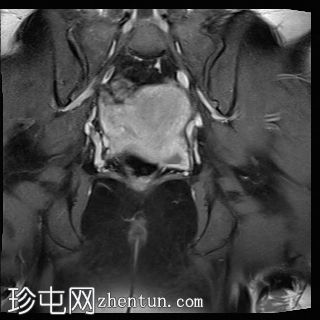

T2脂肪抑制像

冠状位

MRI特征符合剖宫产术后瘢痕子宫内膜异位症,表现为特征性T1高信号伴T1FS持续存在,T2低信号伴内部高信号灶,病灶边缘浸润于腹前壁肌肉内,以及对比增强。

该病灶累及腹白线并浸润腹直肌,主要位于中线左侧,耻骨联合及结节处腹直肌起点上方。

影像学表现符合病灶内出血成分,提示既往剖宫产瘢痕处存在异位子宫内膜组织。

在磁共振成像(MRI)上,瘢痕子宫内膜异位囊肿通常表现出与盆腔子宫内膜异位病灶相似的影像学特征。值得注意的是,它们在脂肪抑制T1加权像上表现为高信号强度区域,对应于异位子宫内膜腺体和出血。